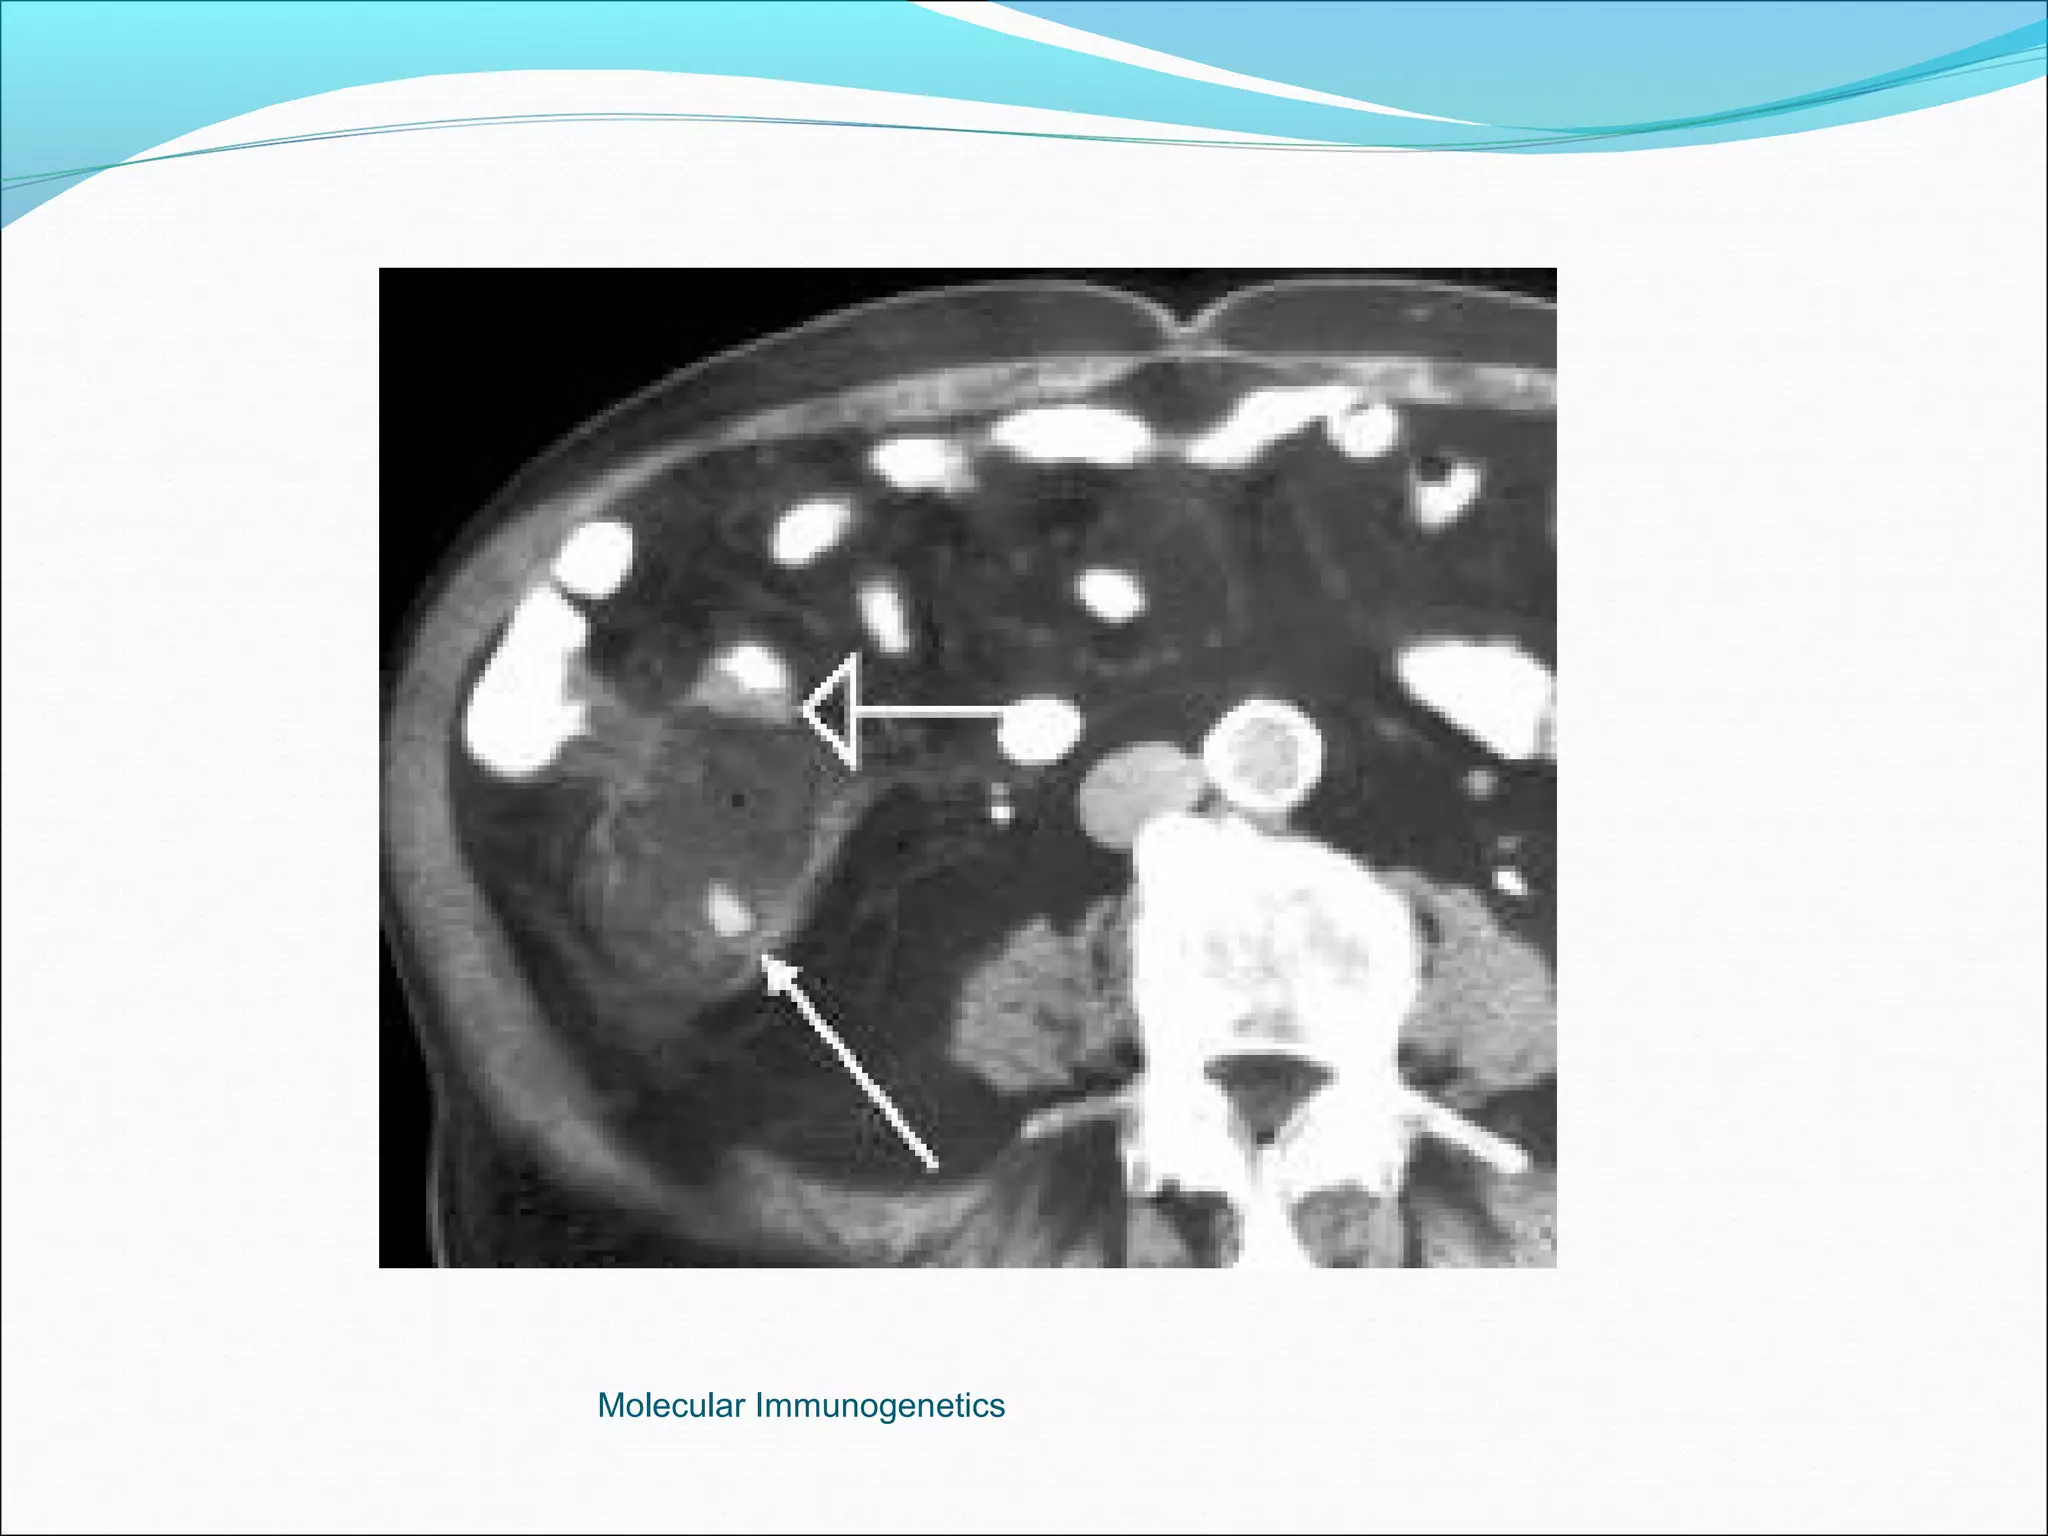

Computer Tomography: More superior to USS in diagnostic accuracy.

The Appendix -Acute Appendicitis Investigations White cell count: high sensitivity 96%, low specificity Urine analysis Plain Xray, nonspecific Ultrasound highly sensitive (80-90%), excludes other pathologies. Computer Tomography: More superior to USS in diagnostic accuracy. Barium enema: Good accuracy, but technically difficult and false positives are common. Laparoscopy Active observation Computer aided diagnosis. Peritoneal lavage Molecular Immunogenetics